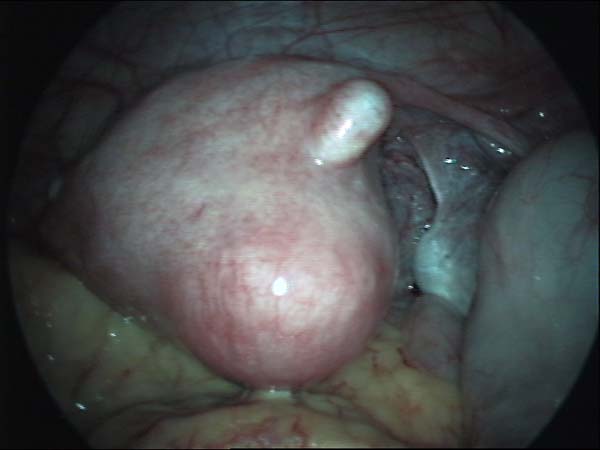

- Laparoscopy Photos 1

- Laparoscopy Photos 2

- Laparoscopy Photos 3

- Laparoscopy Photos 4

Laparoscopy Photos Polycystic Ovaries adhesiolysis IUCD Through Uterine Wall | Dr N Layyous